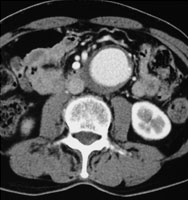

症例14

45歳* 男性

検査異常

【起始・経過】

平成18年2月腹痛精査にて腹部大動脈瘤を指摘され、当院紹介受診。

【既往歴】

高血圧(−) 糖尿病(−) 喫煙歴(30本×20年)

* 性的Activity(+)

【治療計画】

ササッとPercutaneous AAA stent (Gore Excluder/Abbott Prostar closure device)

AAA:Gore Excluder

腎動脈から2cm